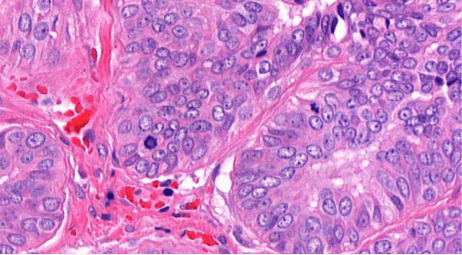

It took 2 seconds for AI to count 210 Ki67+ cells in this breast tissue image

Breast tissue with Ki67 staining